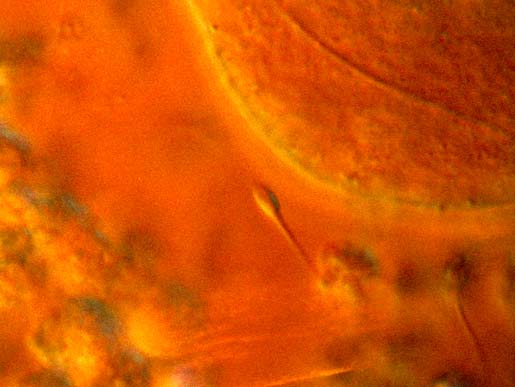

11 (of 11) A light micrograph image showing the encounter between sperm and ovum during in vivo fertilization. A single sperm is seen in centre of the image approaching the circular oocyte. Other competing sperm and cells encompass the corona radiata, which forms a protective halo around the central oocyte, are visible at bottom.

Photo: EDELMANN/SCIENCE PHOTO LIBRARY / IBL Bildbyrå